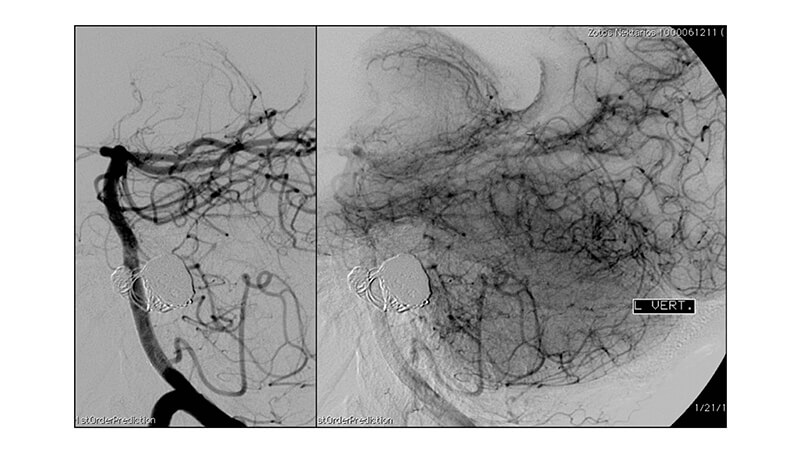

Εικόνα 7, 8: Αγγειογραφία της αριστερής σπονδυλικής αρτηρίας αμέσως μετά την επέμβαση: φαίνεται ικανοποιητική απόφραξη και ασφάλιση των ανευρυσμάτων. Έχει μείνει ελεύθερο το τμήμα του σάκκου κοντά στον αυχένα γιά μελλοντική αποκατάσταση.